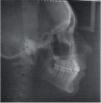

CASE REPORTA patient of 11 years and 4 months of age, mesofacial, who in his medical and dental interrogation referred no clinically relevant information, is presented (Figure 1).